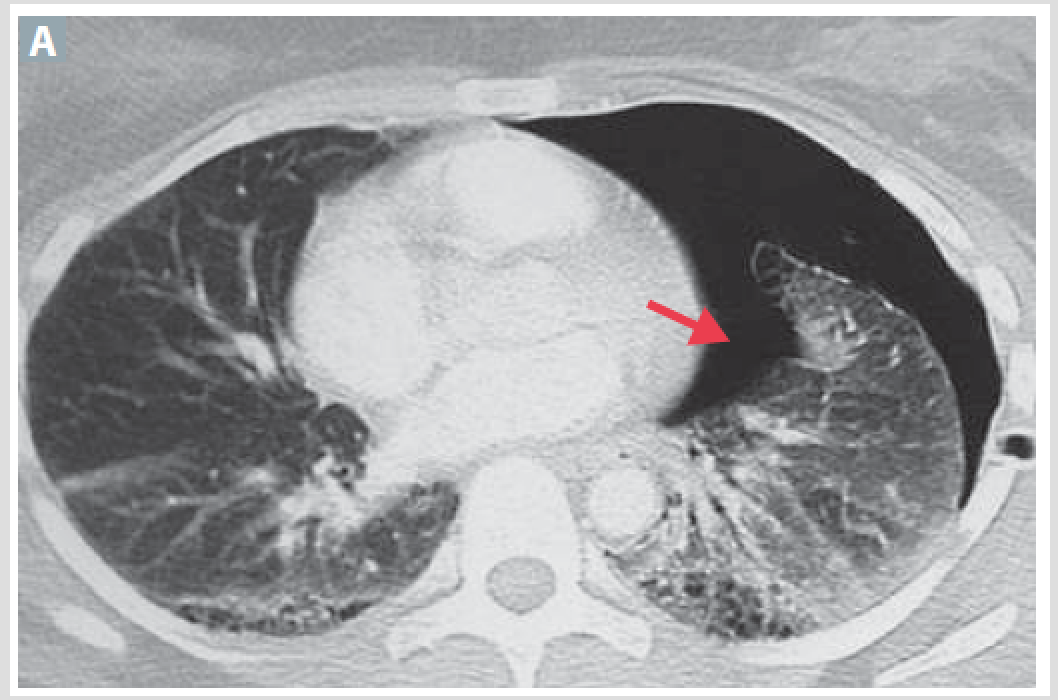

Most common lung cancer in nonsmokers and its activating mutations. CXR shows hazy infiltrates cimilar to pneumonia

Adenocarcinoma

Activating tumors: KRAS, EGFR and ALK